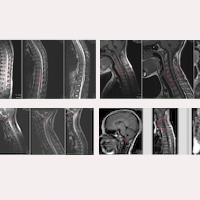

Fig.1. Preoperatorio del Caso 19475: resonancias magnéticas de finales de 2017- encefálica, cervical, dorsal y lumbo-sacra-.

En sus imágenes de Resonancia magnética preoperatorias de 2017 (Fig.1), se podía observar, entre otros hallazgos:

- Descenso de las amígdalas cerebelosas entre el borde inferior del arco posterior de C1 y el borde superior del arco posterior de C2 . Leve dilatación del IV ventrículo.

- Cavidad siringomiélica en C4-D1, muy dilatada.

- Isquemia-edema cervical, dorsal y hasta el Cono medular (pre-siringomielia).